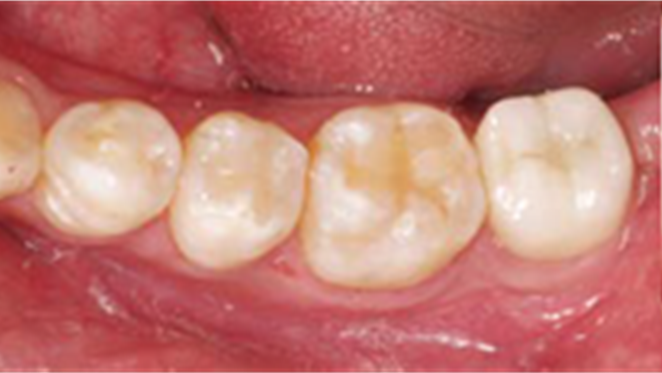

Clinical case: Bone filling into the bottom of deepest thread at 8.0mm AnyRidge fixture

- Courtesy of Dr. Kwang Bum Park -

Keywords

AnyRidge, Knifethread ,extraction socket, ,initial stability ,Allograft, ,osseointegratio ,Dr. Kwang Bum Park, , Mandibular, Single replacement, AnyRidge, Mega-oss,

Products used

Implant system-AnyRidge, Regeneration-Mega-Oss